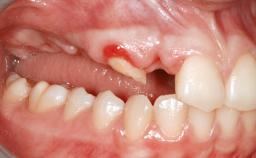

Staged bone augmentation of the alveolar ridge is indicated whenever a proposed implant site is deficient and will not support implant placement with simultaneous grafting. This is particularly true of healed sites presenting with facial flattening of the ridge. Since primary stability cannot possibly be achieved in this situation, it is recommended to use a staged approach with guided bone regeneration (GBR) for correct three-dimensional placement of the implant. In the anterior maxilla, staged GBR procedures are conducted not only to provide adequate bone volume for implant placement but also to restore a proper and stable contour of the orofacial ridge for improved long-term esthetics. A case is presented that demonstrates the technique for single-tooth replacement utilizing a staged approach with a particulate grafting material. A 50-year-old man whose tooth 11 was missing presented for consultation to the Center for Implant Dentistry in January 2010.

Soft Tissue Anatomy Intact Defective

Bone Volume Horizontally and vertically sufficient Horizontally deficient Deficient vertically or deficient vertically AND horizontally

Bone Volume Deficient horizontally, requiring prior grafting